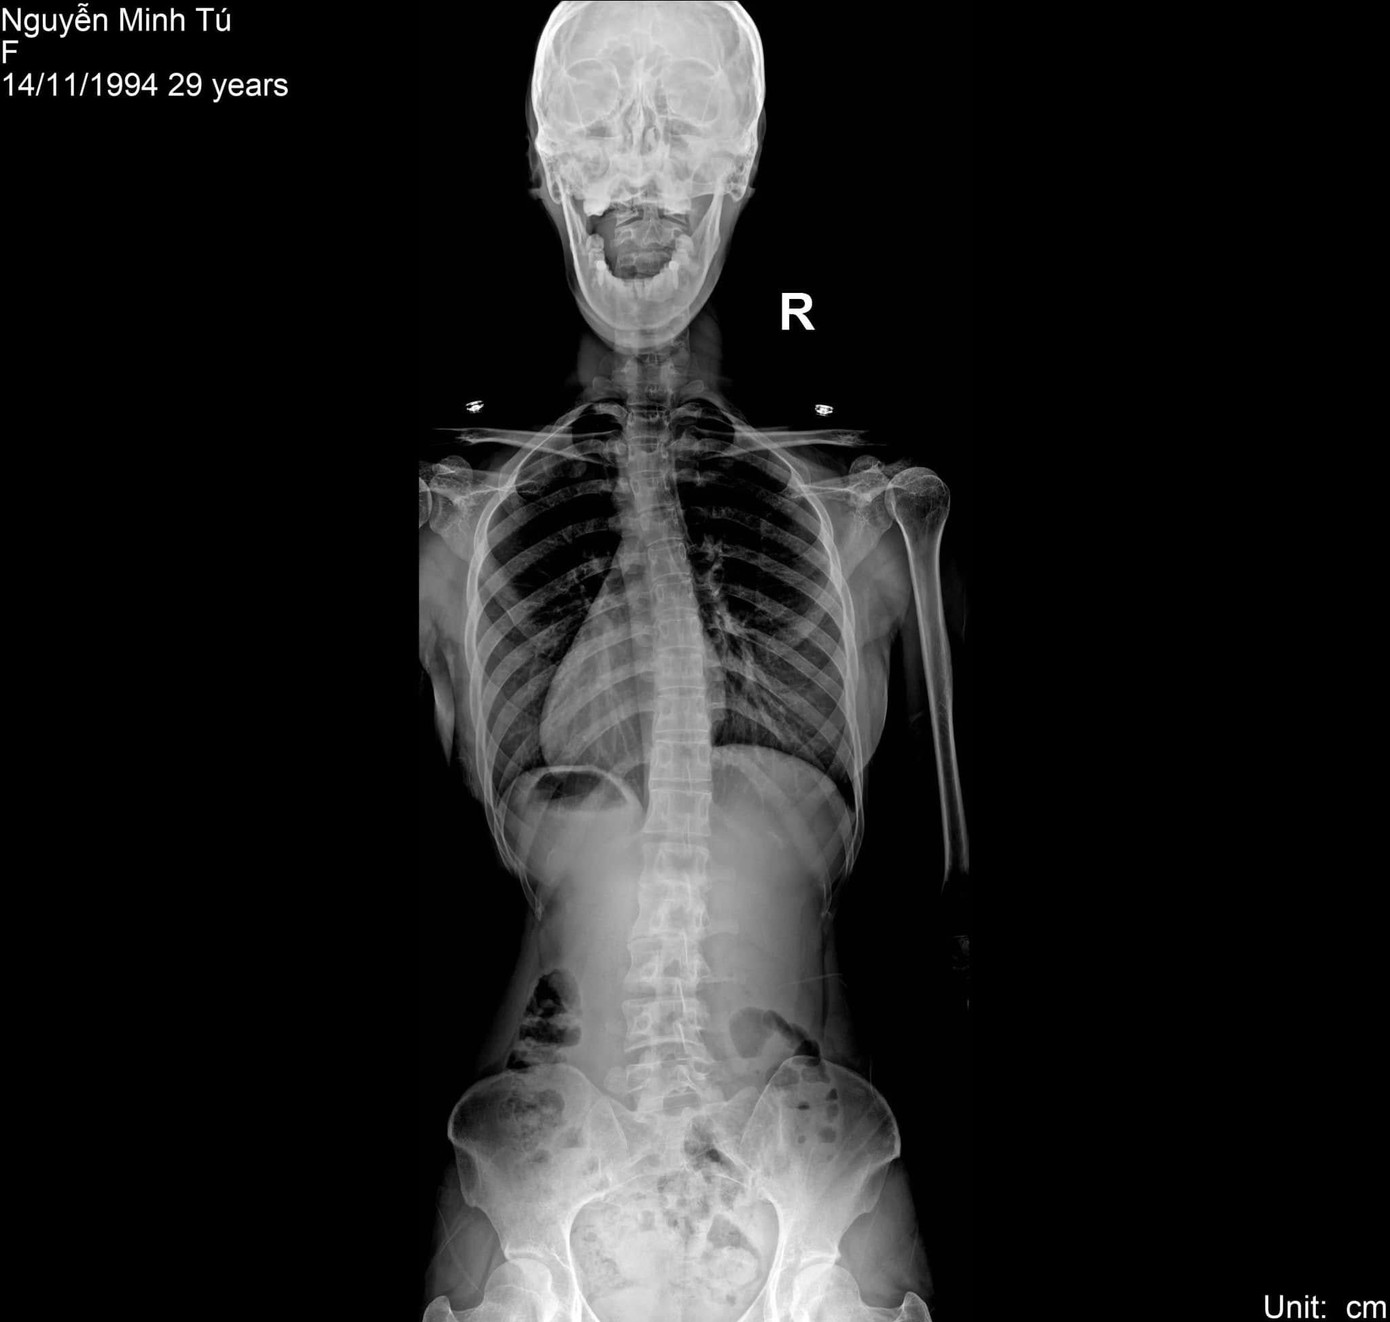

| Minh Tú mắc nhiều bệnh liên quan đến xương khớp như mất đường cong sinh lý cổ, thoái hóa đốt sống cổ, cong vẹo cột sống, thoát vị đĩa đệm... |

Cụ thể, Minh Tú mắc nhiều bệnh liên quan đến xương khớp. Cô mất đường cong sinh lý cổ, thoái hóa đốt sống cổ, cong vẹo cột sống cổ, ngực, thắt lưng, đặc biệt là thoát vị đĩa đệm. Tình trạng bệnh lý của các đốt sống cũng khá nghiêm trọng khi Minh Tú bị thoái hóa đốt sống rất nặng như biến dạng đốt sống, mất xương...